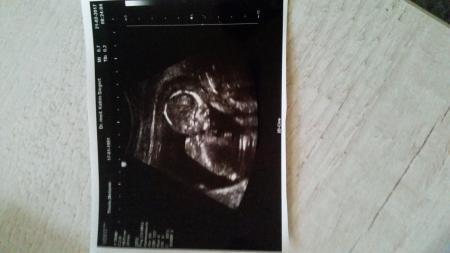

Heute durfte ich auch wieder zur FÄ. Der Pfirsich wird anscheinend mal Stabhochspringer oder Hürdenläufer oder sowas. Es hat sich die ganze Zeit mit den Beinen abgestoßen. Es ist alles super und zeitgerecht entwickelt. Nachher werde ich mal wegen einem Termin für die Feinsono machen. Mein nächster Termin ist der 21.3.17

Bild zu FA-Termin - Forum für August - Mamis

Oh, was für ein schönes Bild ! Und toll, dass alles so gut mit dem Krümel ist

Ein tolles Bild! Und super Neuigkeiten